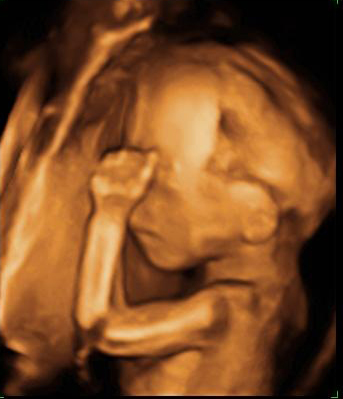

Las ecografías en 2D y en 3D en la semana 20 de embarazo permite diagnosticar algunas malformaciones congénitas fetales, como el labio leporino, que se visualiza en estas imágenes.

Labio leporino (*)

Visualización del mismo caso con ecografía 2D (izquierda) y con ecografía 3D (derecha). La imagen más evidente en la ecografía 3D hace más comprensible para los padres el alcance del problema.